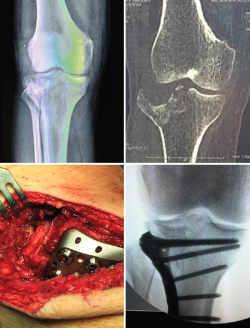

Como ya hemos señalado anteriormente, el uso de la artroscopia de rodilla como asistente quirúrgico ha mejorado en gran medida la reducción articular de estas fracturas y el tratamiento de las lesiones asociadas intraarticulares. Está especialmente indicada en fracturas de tipo I, II y III de Schatzker, que también sintetizaremos con placas de sostén o tornillos canulados con aporte o no de injerto óseo o algún tipo de sustitutivo óseo. La técnica se realiza a través de los portales artroscópicos clásicos anterolateral y anteromedial, y con manguito de isquemia en el muslo. Inicialmente, se drena el hematoma para pasar después a la retirada de cuerpos libres, la evaluación de la superficie articular y el diagnóstico de lesiones meniscales y ligamentosas. Si existe hundimiento articular, se puede emplear una aguja de Kirschner a mano alzada o con ayuda de la guía de reconstrucción del ligamento cruzado anterior desde la cortical tibial hasta en centro exacto del hundimiento de la fractura. Posteriormente, se realiza un túnel tibial a través del cual podemos introducir un dilatador o botador para llevar la superficie articular a la altura adecuada, todo esto bajo visión intraarticular directa y control radioscópico (Figura 4).

Figura 4. Fractura de Schatzker III tratada mediante reducción cerrada asistida con artroscopia y osteosíntesis con 2 tornillos canulados de 6,5 mm.

Los abordajes clásicos para el tratamiento quirúrgico de las fracturas de meseta tibial son el anterolateral, el anteromedial y el longitudinal en la línea media. Este último sería ideal en aquellas fracturas que afecten a la meseta medial y lateral en pacientes por encima de los 50-55 años, ya que posiblemente precisen la implantación de una prótesis total de rodilla por gonartrosis secundaria. La vía anterolateral es la más utilizada en virtud de la mayor frecuencia de las fracturas del platillo externo que afectan a la columna anterolateral (Figura 5). La vía anteromedial se emplea para fracturas exclusivamente del platillo interno con afectación de la columna anteromedial. Para fracturas bituberositarias anteriores, podemos emplear un doble abordaje lateral y medial, o decantarnos por una única vía longitudinal en la línea media.

Figura 5. Tratamiento de una fractura de meseta tibial mediante fijación interna y osteosíntesis.